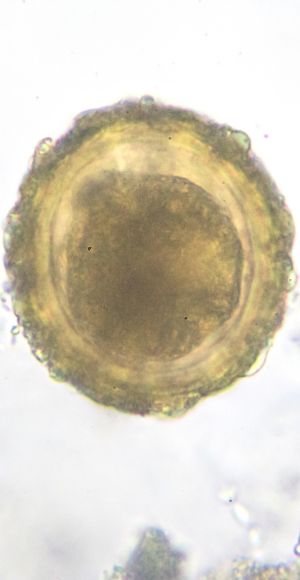

At Gaia Fertility, every potential egg donor undergoes a thorough testing and screening process before approval, ensuring the highest quality eggs for the donation journey.

The screening procedure assesses key parameters, including the donor’s age, genetic profile, physical health, and mental well-being.

Only after these comprehensive checks are completed does the egg donation process proceed, utilizing the most advanced medical facilities and techniques available.

Once the medical evaluations are finalized, our egg donation specialists carefully review each donor’s profile to ensure suitability.